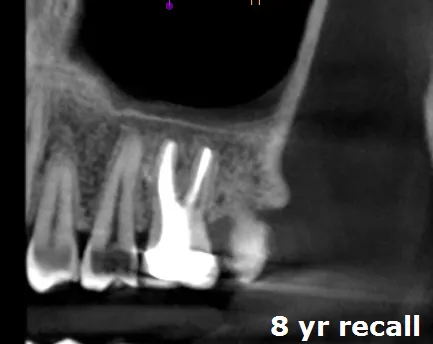

At 8 year follow-up, this tooth demonstrates excellent healing:

• Pocket depth reduced from 9mm to 4mm (clinically healthy)

• Radiographic bone regeneration visible around apex

• No symptoms, no swelling, no mobility

• Tooth fully functional in occlusion